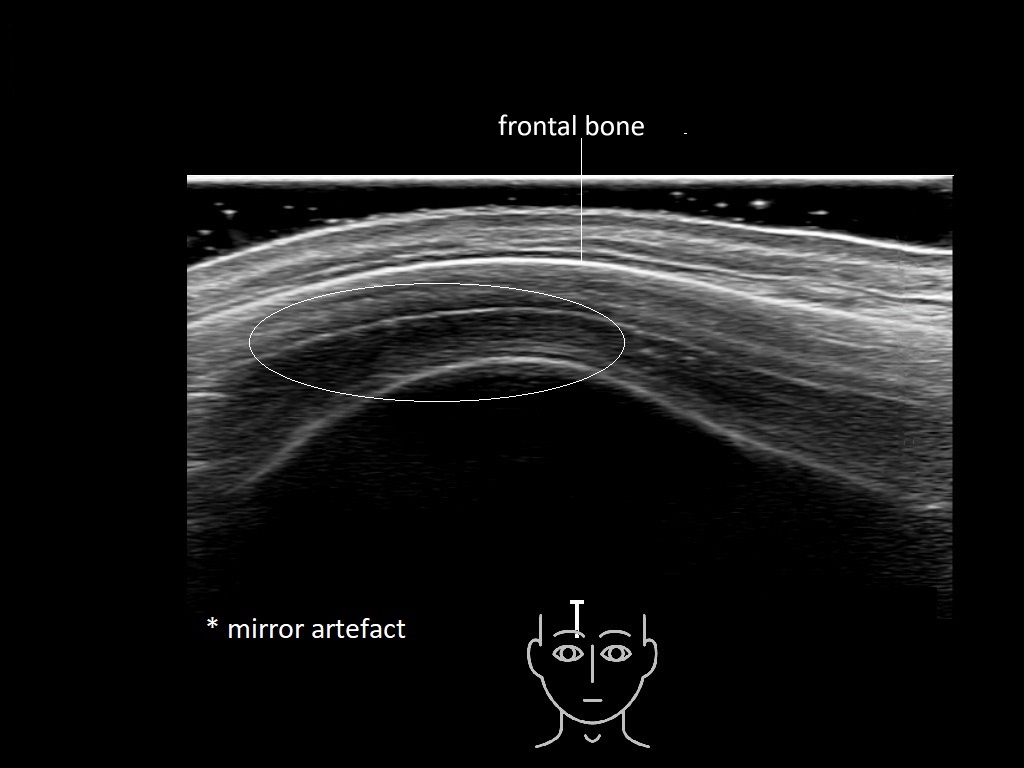

In this section you will learn more about the different layers of the face with the use of ultrasound. When you click on the secondary ultrasound image, you will see the different structures as an overlay. This will help to train yourself to recognize the different layers of the face.

Study the first image to recognize the different layers. If you are sure about the layers, swipe to the second image to view the answer (if applicable).